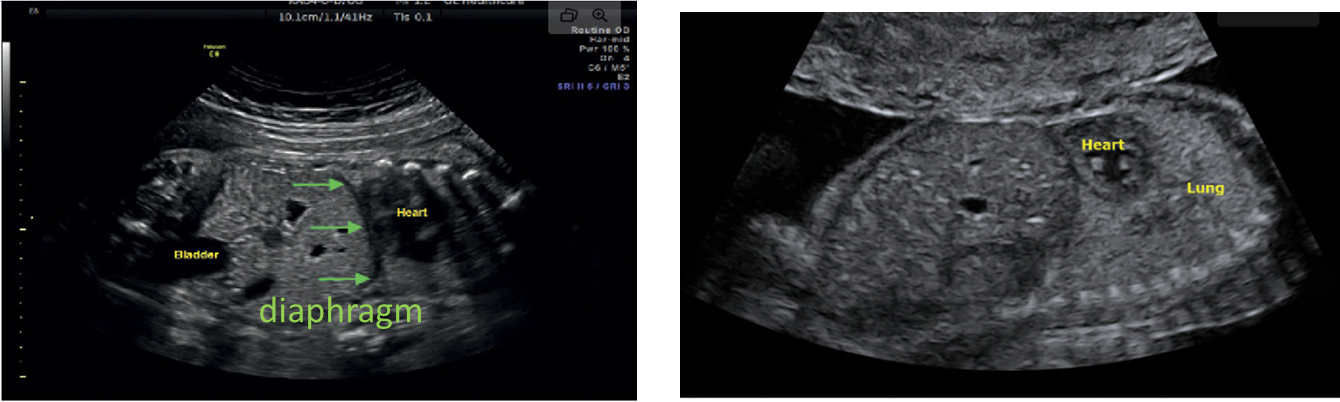

echotexture of lungs

symmetrically homogeneous

increases as gestation progresses

normally what is closest to anterior abdominal wall

right ventricle

what is closest to spine

left atrium

4 chamber heart should sit at a ___ degree angle and take up about ____ of the chest

45 degree

1/3

___ of the herat located in left chest with apex pointing ____

2/3

left

checklist for 4 chamber heart

situs

heart position

cardiac size

squeeze ok?

chamber ID and symmetry

septum appearance

AV valve offset

foramen ovale flap

area behind heart

rate and rhytm

what is it called when organs in the chest and abdomen may be in the wrong position

heterotaxy

heart and stomach on ____ side